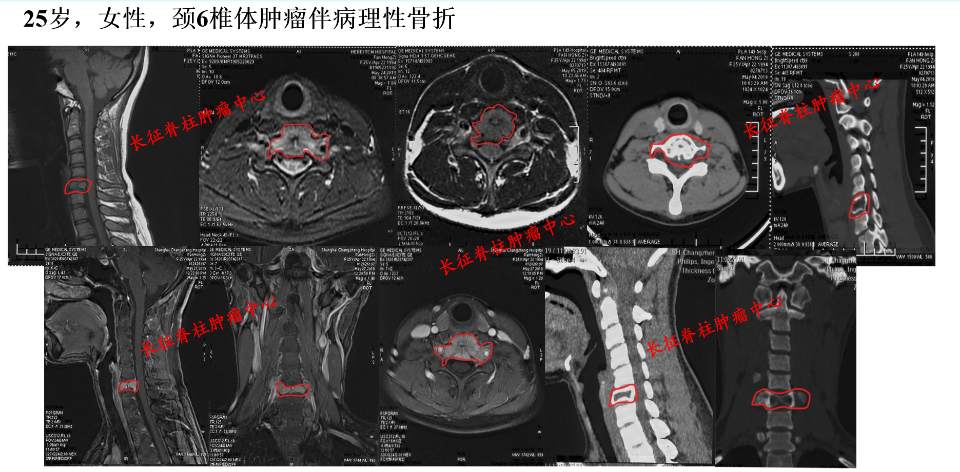

图一.青年女性,颈肩部剧烈疼痛,C6椎体溶骨性破坏,伴发病理性骨折,存在瘫痪风险。